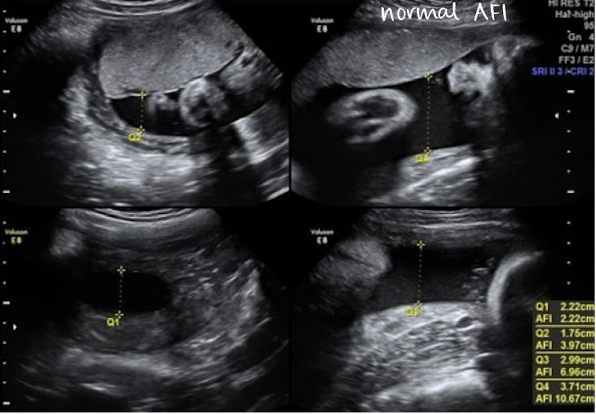

AF measurement method: amniotic fluid index (AFI)

most used method for quantifying amniotic fluid volume

uterine cavity is divided into 4 equal quadrants

largest pocket in each quadrant is measured (AP) in SAG plane and added together

transducer should be perpendicular to table, not curved skin surface

exclude fetal limbs and umbilical cord loops )can use color Doppler)

do NOT measure through a structure

AF measurement method: AFI example

normal AFI values

10 cm < AFI < 20 cm

should be between 10-20 cm